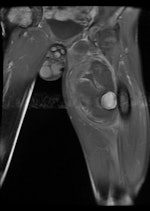

Plain radiography and CT are the most commonly used modalities for imaging of gunshot wounds, but angiography and MRI are playing an increasing role, according to research presented at the 2011 U.K. Radiological Congress (UKRC) in Manchester.

Doctors involved in the care of these patients need to understand the patterns and mechanisms of the injuries, he explained. To accurately interpret images of gunshot wounds, a basic knowledge of ballistics is important, especially the factors affecting the extent and type of tissue damage. Such knowledge is useful not only for evaluating acute injuries but also for determining the path of the missile, awareness of missile fragmentation, and embolization, thus contributing to the overall clinical, and often the forensic, picture.